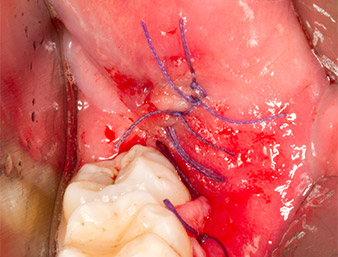

Tras una anestesia local y por conducción, el campo quirúrgico se abrió mediante los tejidos blandos para tener un acceso bucal-retromolar y se dejó expuesto (figura 3).

A continuación, el tejido óseo autógeno (figura 13) se incorporó en el alvéolo y en el defecto óseo circundante (figura 14). Un velo de colágeno sirvió de protección para el nervio expuesto y cubrió las virutas óseas hasta el nivel del hueso (figura 15). Se aplicaron puntos de sutura con hilos Vicryl de grosor 4.0, que cerraron los tejidos blandos abiertos (figura 16). Tras la operación, se prescribió un preparado de ibuprofeno (Seractil 400 mg 3x1) y un antibiótico con amoxicilina y ácido clavulánico (Augmentine 1g 2x1).